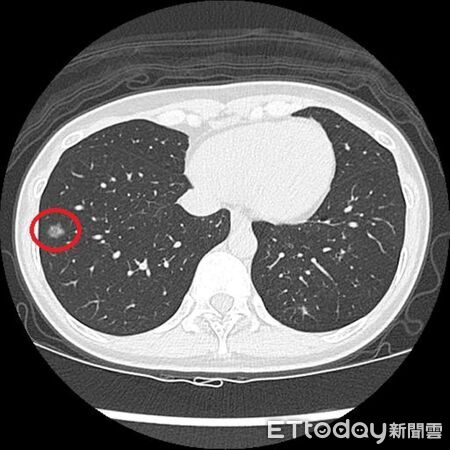

▲LDCT檢查發現陳小姐右側肺部有一顆1.2公分大的毛玻璃結節 。(圖/台北慈院提供)

年約40歲的陳小姐過去有抽菸習慣,近2年戒掉,日前身體雖無不適,但符合公費低劑量電腦斷層(LDCT)篩檢條件,決定去檢查,結果在右肺發現一顆約1.2公分的毛玻璃結節,經手術切除後,病理檢查確診為肺癌;醫師說,此案例凸顯即使已戒菸且無症狀,仍可能有早期肺癌,民眾不能輕忽。

台北慈濟醫院胸腔外科主治醫師洪嘉聰說,陳小姐平時定期留意自身健康狀況,此次經LDCT 篩檢後轉介而來,隨後以單孔胸腔鏡微創手術切除病灶,病理證實為肺腺癌第一期,術後恢復情形穩定,目前持續定期回診中。